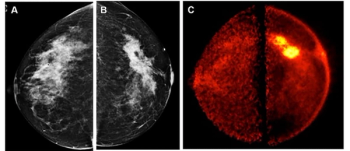

In a recent interview, Vivianne Freitas, M.D., discussed new research findings on positron emission mammography (PEM), pertinent benefits of the technology and its potential as a viable alternative in the future to conventional imaging techniques for breast cancer screening.

Findings from a new pilot study showed that low-dose positron emission mammography (PEM) detected 96 percent of malignant index lesions and had a 46 percent lower false-positive rate in comparison to breast MRI.